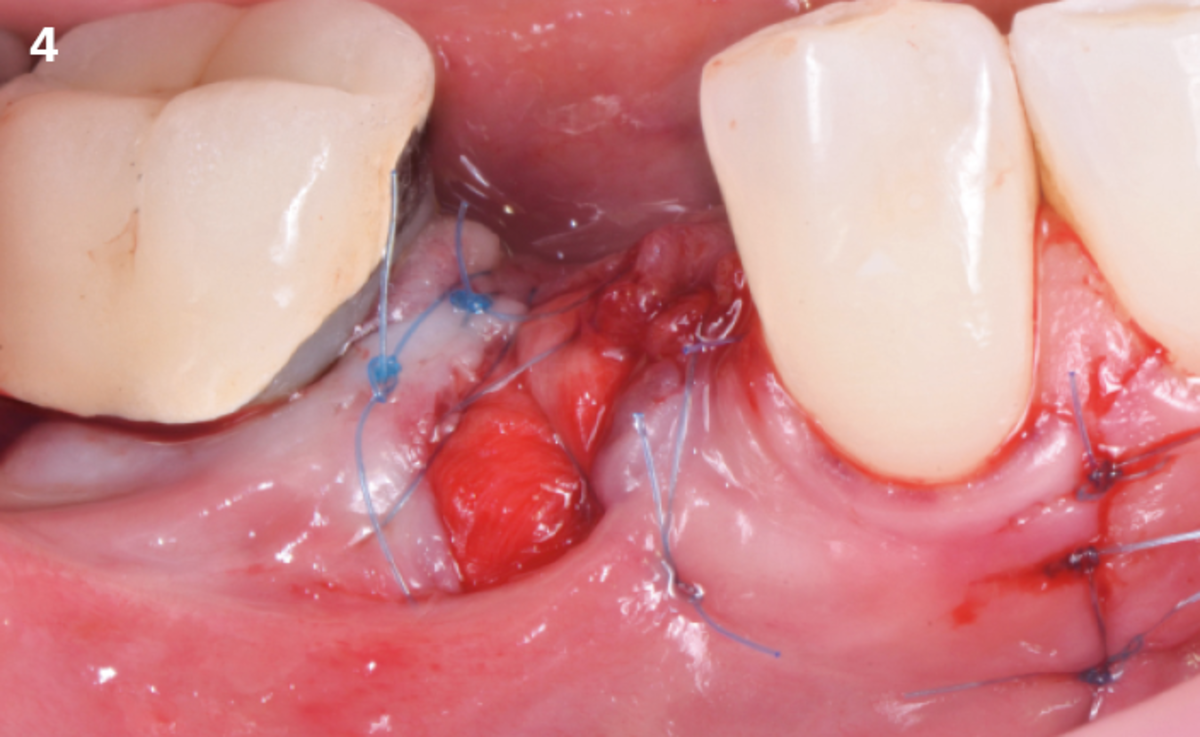

"After the extraction, I realized that the buccal wall was missing and I had to leave the membrane exposed. The regenerative potential of the site could be poor, so I decided to boost the biomaterials’ effect with polynucleotides and hyaluronic acid."

The patient (45 years old, female, non-smoker, no previous pathologies) is referred for extraction of tooth 45 and immediate implant placement. The site showed an increased probing depth and a marked bone loss.